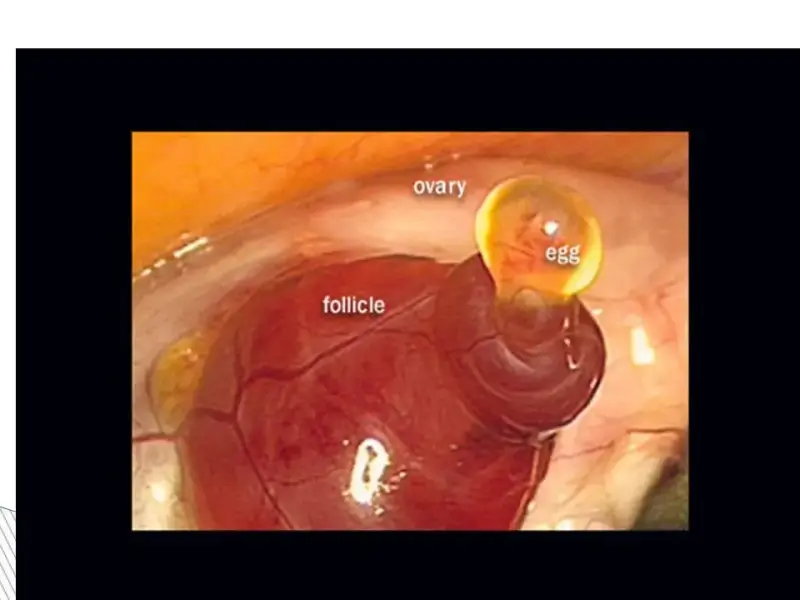

Яичники – центральное звено репродуктивной системы женщины. В яичниках заложены клетки, несущие наследственную информацию о будущем потомстве, позволяющие женщине иметь генетически своих детей.

Как выглядит яичник? Яичник – это парный эндокринный орган, расположенный по бокам от матки, рядом с ампулярными отделами маточных труб, размерами в среднем 2,5–-4 см, они имеют плоское овальное тело. Одним краем яичник прикреплен к брыжейке, там расположены ворота яичника, а другим связан с маткой собственной связкой.

Яичники имеют два слоя – корковый и строму. В корковом веществе происходит созревание фолликулов, которые содержат яйцеклетки (женские половые клетки).

Фолликулы имеют разный размер от микроскопических до 1 см. Крупные фолликулы – предовуляторные, т.е. готовые к овуляции. Обычно в менструальном цикле женщины созревает один фолликул, реже 2 или 3. Фолликул созревает к середине менструального цикла женщины. В этот момент под действием большого количества гормонов гипофиза и яичников происходит разрыв фолликула, и яйцеклетка выходит в брюшную полость. В период своего роста (до момента овуляции) фолликул становится эндокринной железой – он вырабатывает большое количество женских половых гормонов – преимущественно, эстрогены. После овуляции фолликул резко меняет свою структуру и трансформируется в желтое тело – оно начинает вырабатывать прогестерон – гормон второй фазы менструального цикла. Прогестерон – это и основной гормон беременности. Поэтому если происходит оплодотворение овулировавшей яйцеклетки, то желтое тело увеличивается в размерах и поддерживает уровень прогестерона до тех пор, пока эту функцию не возьмет на себя плацента (т.е. до 12 недель беременности). Если же оплодотворение не произошло, желтое тело постепенно угасает. На 28-ой день, количество гормонов резко снижается – начинаются очередные месячные. Далее цикл повторяется сначала – и так на протяжении всего репродуктивного периода в жизни женщины.

Овуляция.

Примерно на 12–14 день от начало менструаций происходит овуляция – выход созревшей яйцеклетки из яичника. Дальше яйцеклетка движется по маточной трубе. Эндометрий утолщается и готовится к началу питания яйцеклетки.